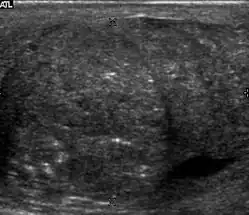

Patients with testicular lymphoma are usually old aged around 60 years of age, present with painless testicular enlargement and less commonly with other systemic symptoms such as weight loss, anorexia, fever and weakness. Bilateral testicle involvements are common and occur in 8.5% to 18% of cases. At sonography, most lymphomas are homogeneous and diffusely replace the testis [Fig. 7]. However focal hypoechoic lesions can occur, hemorrhage and necrosis are rare. At times, the sonographic appearance of lymphoma is indistinguishable from that of the germ cell tumors [Fig. 8], then the patient's age at presentation, symptoms, and medical history, as well as multiplicity and bilaterality of the lesions, are all important factors in making the appropriate diagnosis.